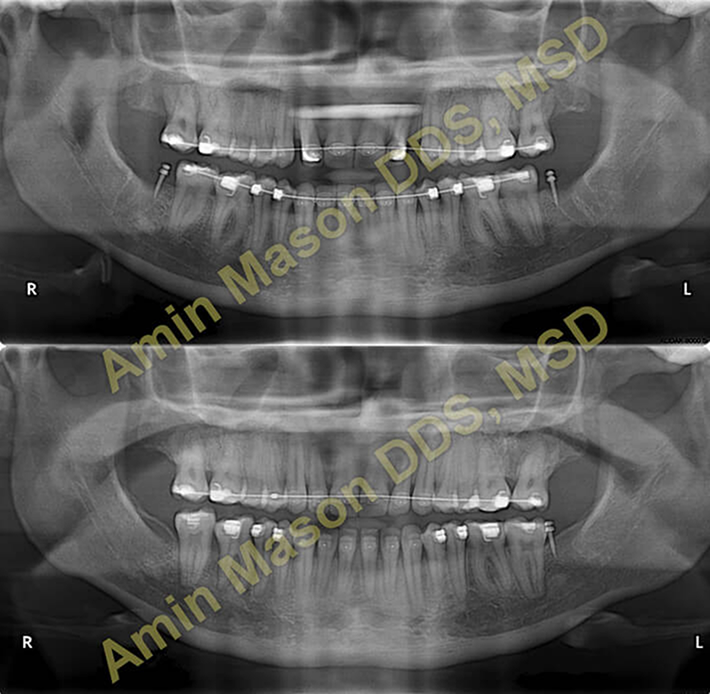

Class III / Underbite Correction Case

Adult patient with severe underbite and skeletal class III, patient was treated non-surgically using multiple TADS.